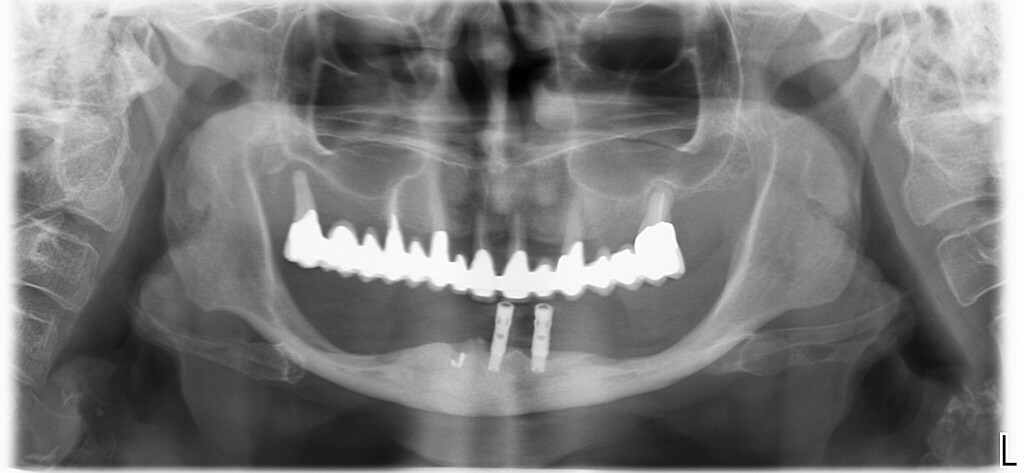

Mandibola atrofica Formazione Odontoiatrica

La domanda era se, secondo me, si potesse eseguire una riabilitazione fissa su impianti. Questo articolo, e soprattutto il video che segue, vogliono essere i miei suggerimenti al collega e a chiunque altro volesse ritenerli utili.

Parleremo del trattamento di questa mia paziente, trattata cinque anni fa, che mi sembra molto simile a quello del collega.

Mandibola atrofica Formazione Odontoiatrica 2